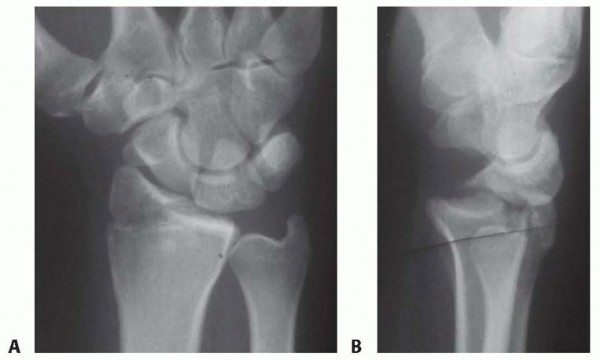

Reduction and Stabilization of the Distal Radioulnar Joint following Galeazzi Fractures